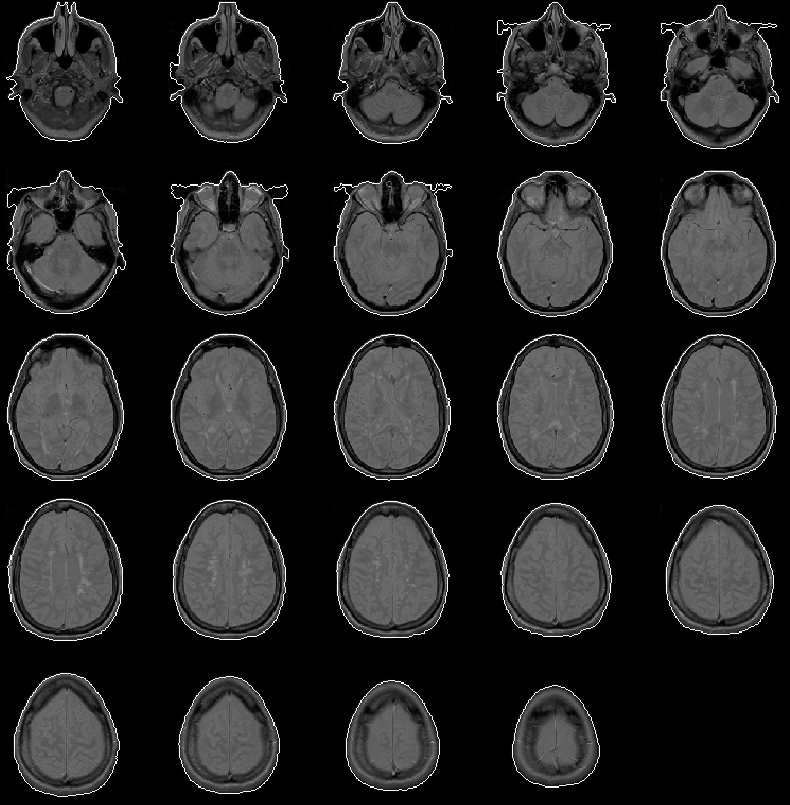

The boundary of the head mask produced for Data Set 1 is overlaid on the PD-weighted volume in Figure 8.6. For the most part, the mask is extremely accurate.

Figure 8.6: The head mask for MRI Data Set 1 overlaid on the PD-weighted scan.

In some slices, the mask does not cover the entire head. This anomaly occurs because the mriFillBlobs operator in the Segment Head igraph fails to fill in regions that are not completely enclosed, even at the image edges. The problem might be fixed by treating the image edge as an enclosing boundary.

This problem has not been addressed because it has little effect on the final results of the intracranial boundary detection algorithm. The Generate Initial Brain Mask process uses the centroid and bounding box of the head mask in each slice. The inaccuracies in the mask affect these features only slightly.